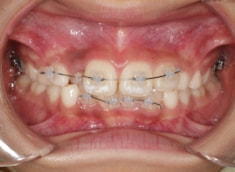

治療中